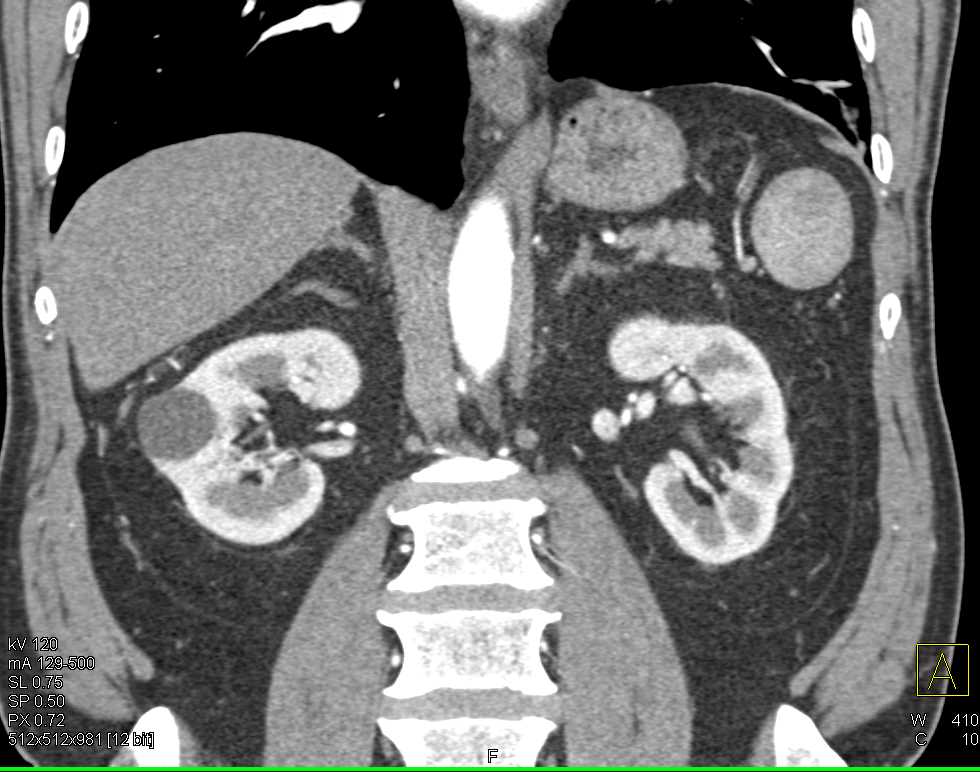

Carcinoid Tumor in the Root of the Mesentery with Desmoplastic Reaction and Carcinomatosis